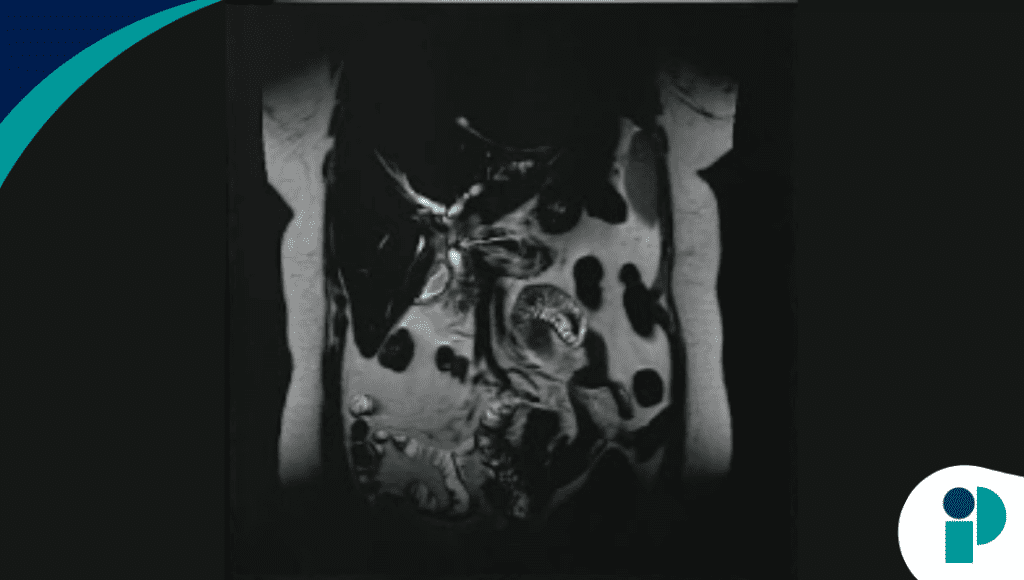

Los estudios de imagen mostraron dilatación de la vía biliar, y la colangiopancreatografía por resonancia magnética evidenció estenosis biliares irregulares con dilatación intrahepática, hallazgos más compatibles con un proceso no anastomótico.